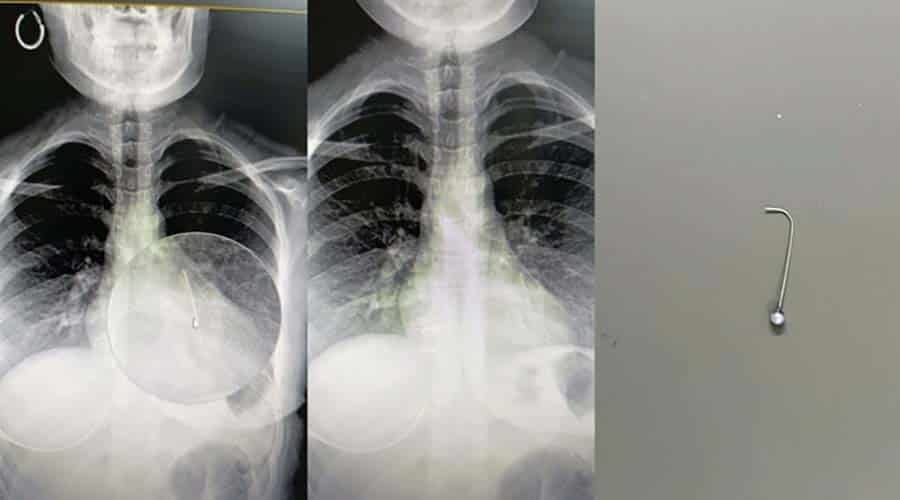

Haber: Cuma Sarı – Şanlıurfa’da 16 yaşındaki kız çocuğunun eşarbını düzelttiği sırada yuttuğu toplu iğne, yapılan ameliyatla saplandığı akciğerden alındı.

Çocuk Cerrahisi Uzmanı Op. Dr. Mehmet Emin Balcıoğlu tarafından bronkoskopi yöntemiyle sol akciğere saplanan toplu iğne yaklaşık 1 saat süren başarılı operasyonla çıkarıldı.

“16 yaşındaki hastamız, öğle saatlerinde başörtüsünü düzeltirken toplu iğneyi yutmuş. Öğlenden beri Şanlıurfa Devlet Hastanesi’nde bekliyormuş. Şanlıurfa ve çevre illerdeki hastaneler hastayı kabul etmemiş. Bronkoskopi yöntemiyle sol akciğerin alt kısmına yerleşmiş iğneyi çok şükür başarıyla çıkardık. Hastamızın durumu iyi, birkaç gün misafir ettikten sonra sağlıklı şekilde evine göndereceğiz.”